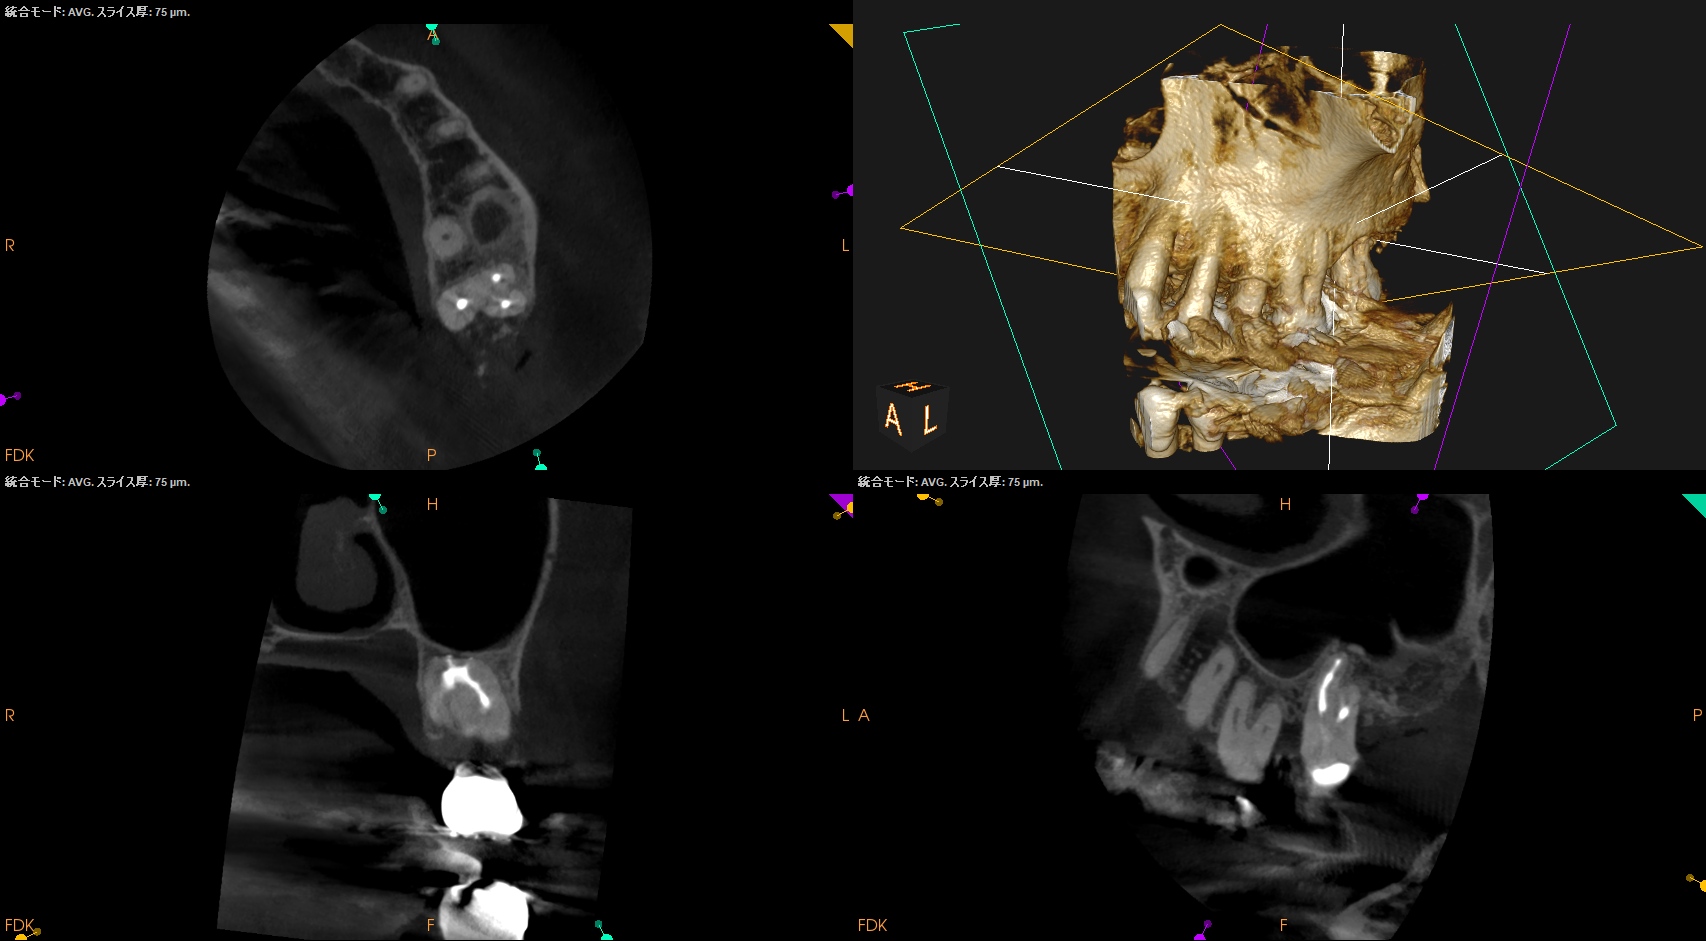

#15 RCT 1yr recall(2025.10.28)

MB

DB

P

初診時と比較した。

根尖病変、

術前の臨床症状、

術前の歯周ポケット

は完治した。

最終補綴もOKだ。

この日で経過観察も終診とさせていただいた。